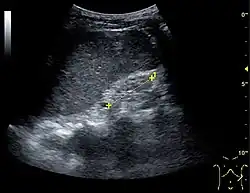

Figure 1. Normal adult kidney. Measurement of kidney length on the US image is illustrated by '+' and a dashed line. *Column of Bertin; ** pyramid; *** cortex; **** sinus.[1]

The length of the adult kidney is normally 10–12 cm, and the right kidney is often slightly longer than the left kidney. The adult kidney size is variable due to the correlation with body height and age; however, normograms for pediatric kidney size are available.[1]

Cortical thickness should be estimated from the base of the pyramid and is generally 7–10 mm. If the pyramids are difficult to differentiate, the parenchymal thickness can be measured instead and should be 15–20 mm (Figure 3). The echogenicity of the cortex decreases with age and is less echogenic than or equal to the liver and spleen at the same depth in individuals older than six months. In neonates and children up to six months of age, the cortex is more echogenic than the liver and spleen when compared at the same depth.[1]

The kidney is divided into parenchyma and renal sinus. The renal sinus is hyperechoic and is composed of calyces, the renal pelvis, fat and the major intrarenal vessels. In the normal kidney, the urinary collecting system in the renal sinus is not visible, but it creates a heteroechoic appearance with the interposed fat and vessels. The parenchyma is more hypoechoic and homogenous and is divided into the outermost cortex and the innermost and slightly less echogenic medullary pyramids. Between the pyramids are the cortical infoldings, called columns of Bertin (Figure 1). In the pediatric patient, it is easier to differentiate the hypoechoic medullar pyramids from the more echogenic peripheral zone of the cortex in the parenchyma rim, as well as the columns of Bertin (Figure 2).[1]

In the longitudinal scan plane, the kidney has the characteristic oval bean-shape. The right kidney is often found more caudally and is slimmer than the left kidney, which may have a so-called dromedary hump due to its proximity to the spleen. The kidney is surrounded by a capsule separating the kidney from the echogenic perirenal fat, which is seen as a thin linear structure.[1]